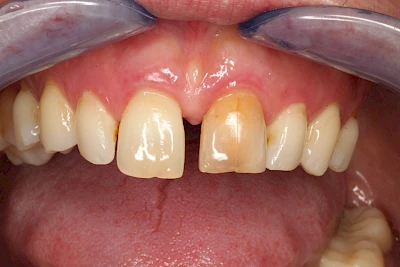

Dunkle bzw. Rötliche Verfärbung

Ist ein einzelner Zahn deutlich dunkler als die Nachbarzähne kann das ein Zeichen sein, dass der Nerv abgestorben ist. Unter Umständen wurde bereits eine Wurzelkanalbehandlung vom Zahnarzt durchgeführt. Eine Abklärung durch den Zahnarzt ist in jedem Fall sinnvoll.